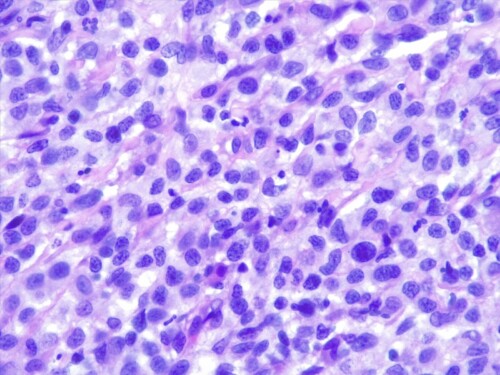

Le derme est envahi par une plage cellulaire dense diffus, peuplé majoritairement de cellules rondes indépendantes présentant une allure histiocytaire, des granulocytes neutrophiles et quelques cellules lymphoplasmocytaires.. Elles sont dotées d’un noyau discrètement plicaturé à chromatine à tendance hyperchromatique finement mottée autour de plusieurs nucléoles. Le cytoplasme est abondant acidophile et présente des limites imprécises. On observe également une anisocaryose, et parfois des cellules plurinucléées, et une forte activité mitotique. Les annexes cutanées sont atrophiées et emprisonnées au sein de cet infiltrat. Aucun élément figuré pathogène parasitaires ou fongiques n’est visible sur la réaction au PAS ni sur les différents de section effectués. L’épiderme est ulcéré et hyperplasique.

L’histopathologie se caractérise par un infiltrat dermique et sous-cutané histiocytaire mal délimité, non-encapsulé. Cet infiltrat se compose de cellules rondes à polygonales à rapport nucléo-cytoplasmique bas, et cytoplasme éosinophilique ou finement granuleux, un noyau ovale ou indenté et chromatine mottée. Un épithéliotropisme – agrégats intra-épidermiques de cellules tumorales – est présent dans une proportion non négligeable , 42% selon la même étude.

Des cellules plurinucléées sont parfois notées, associées à un nombre de mitoses variable. La présence d’atypies cellulaires (pléomorphisme, anisocytose et anisocaryose), d’un index mitotique élevé et de la présence d’emboles intra-lymphatiques ou intravasculaires sont associées à des formes disséminées.